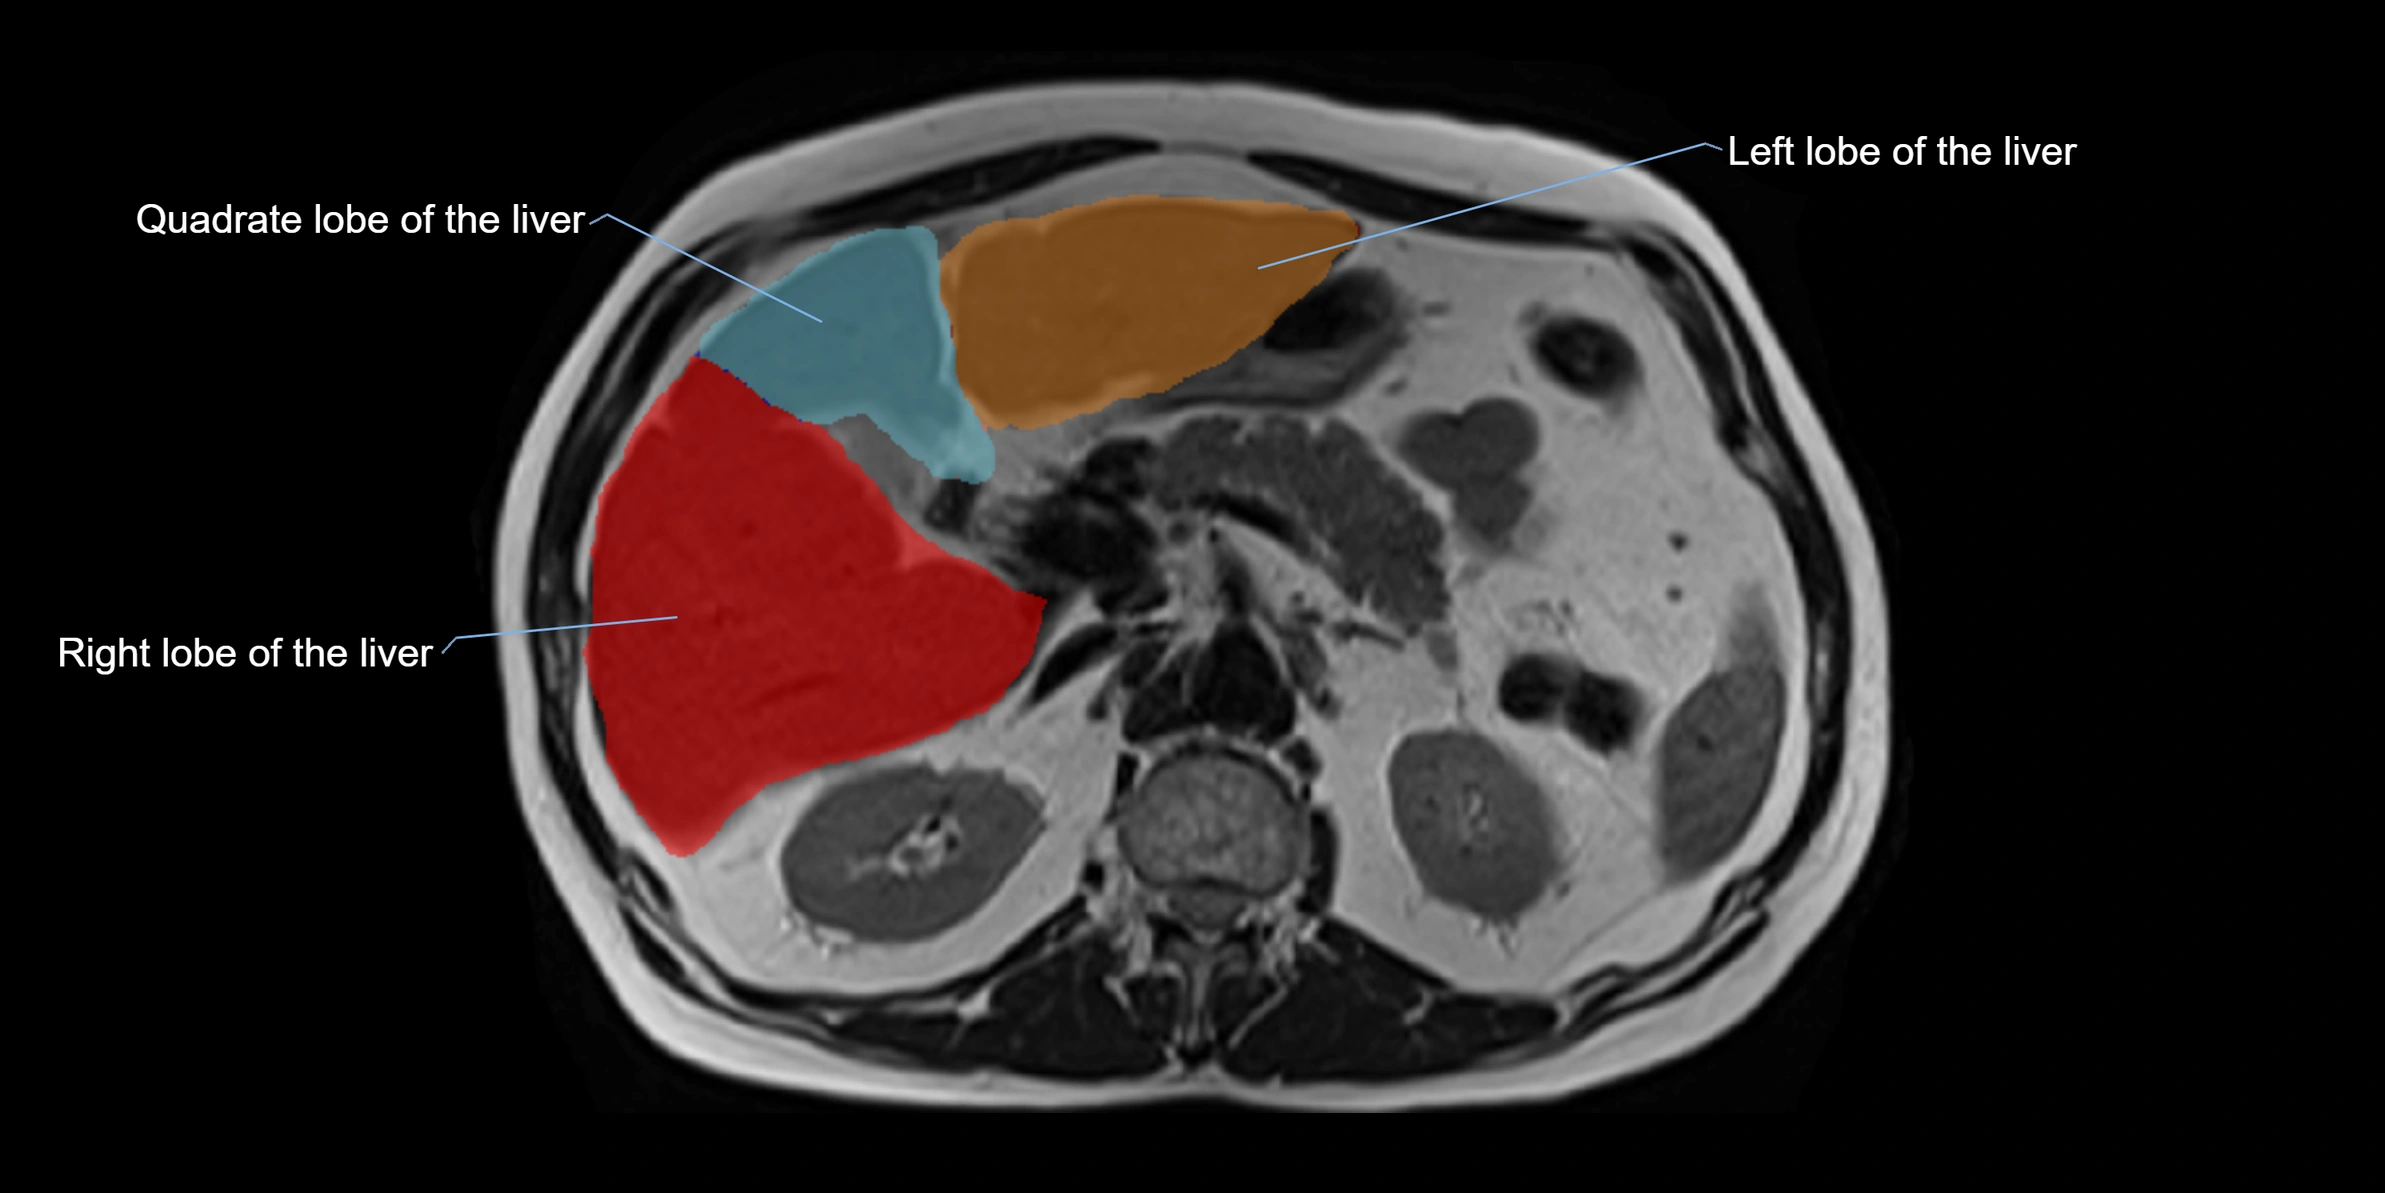

The caudate lobe of the liver is a distinct anatomical subdivision of the liver, designated as segment I in Couinaud’s classification. It lies on the posterior surface of the liver, between the fissure for the ligamentum venosum (left boundary) and the groove for the inferior vena cava (IVC) (right boundary). Superiorly, it is related to the posterior liver surface, and inferiorly it is separated from the left lobe by the porta hepatis.

MRI Appearance

T1 Fat-Saturated (Pre-contrast):

• Caudate lobe appears as intermediate signal parenchyma against suppressed fat

T1 Fat-Saturated Post-Contrast (Gadolinium):

• Homogeneous enhancement in normal parenchyma during portal venous phase

• Lesions (HCC, metastasis, hemangiomas) enhance with characteristic dynamic patterns

• Important in detecting vascular invasion and caudate hypertrophy